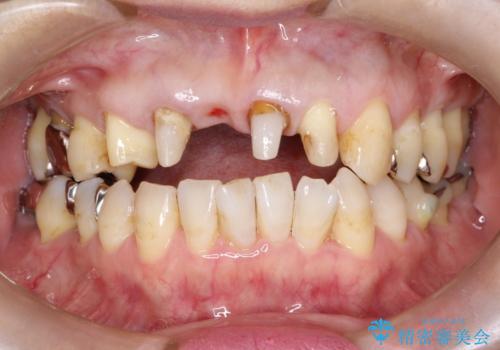

矯正を併用した前歯のセラミックブリッジ治療

- 上顎前歯をきれいにしたいとのことで来院されました。

レントゲンを撮影すると保存が難しい歯がありました。

またがたつきの度合いから歯を1本抜歯して矯正治療を行いセラミックブリッジを装着することで、審美的・機能的改善を行う計画としました。